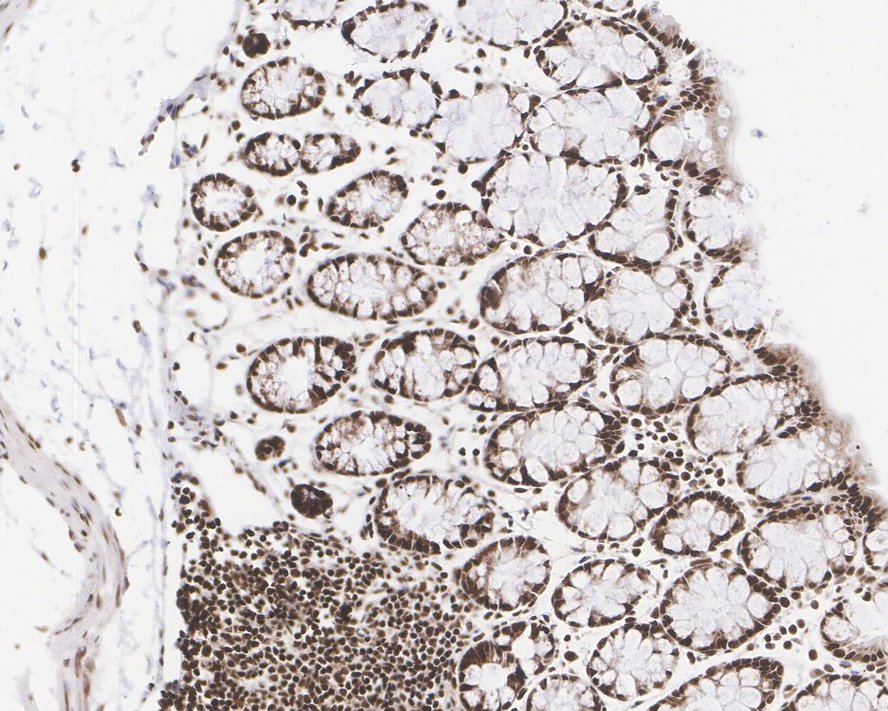

NCOA4 Recombinant Rabbit Monoclonal Antibody [PSH05-45] - BSA and Azide free

Catalog# HA751004

IHC-P

Human

-

Mouse

Rat

HA722283